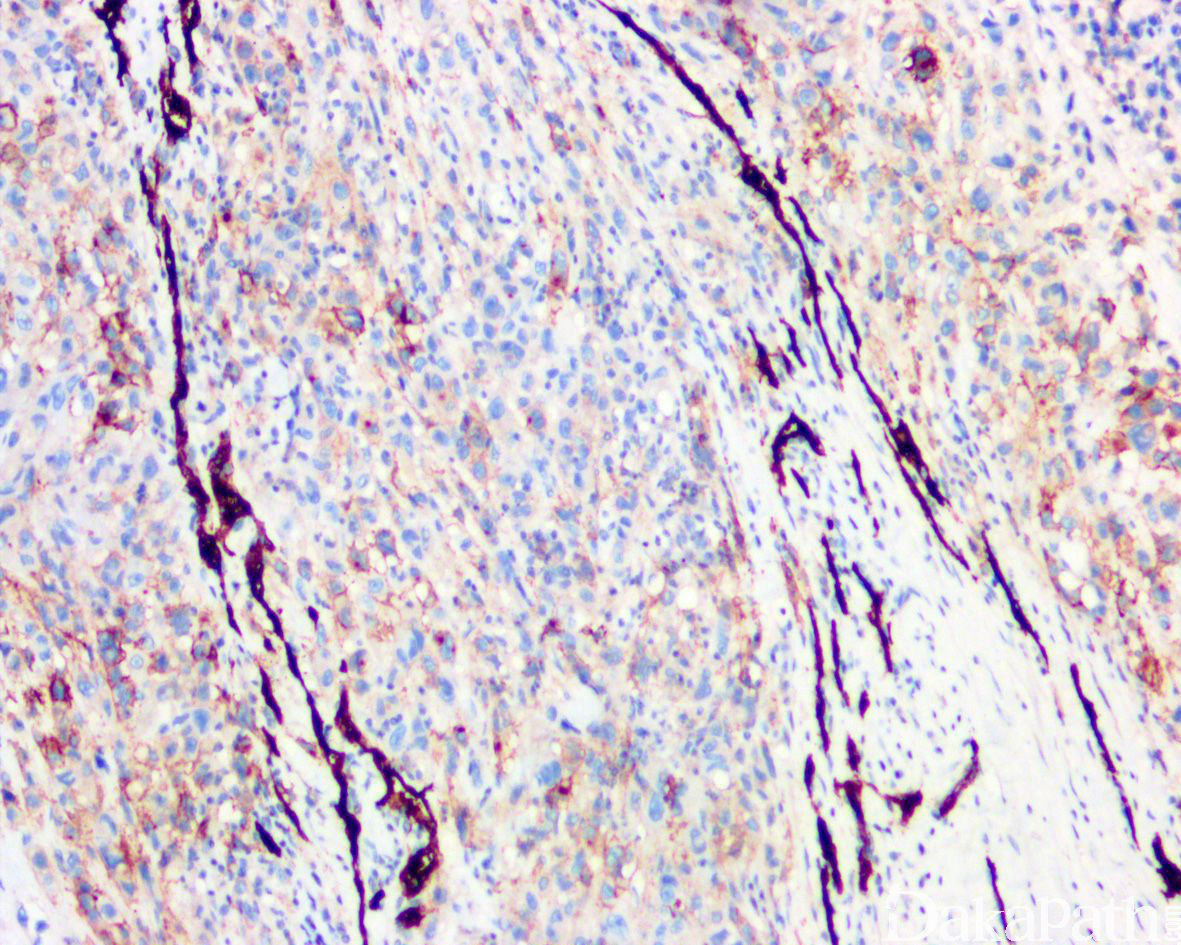

免疫组织化学染色:

瘤细胞 AE1/AE3. EMA、CK8. CK19 和 vimentin 常阳性,50%-70%病例 CD34 阳性,95%以上显示 SMARCB1(INI1)表达丢失;部分病例可表达 MSA、α-SMA、S-100. ERG 和 NSE,偶尔表达 SALL4,—般不表达 CK20. desmin、NF、CEA 和 CD31。

95%以上可见 SMARCB1 基因缺失